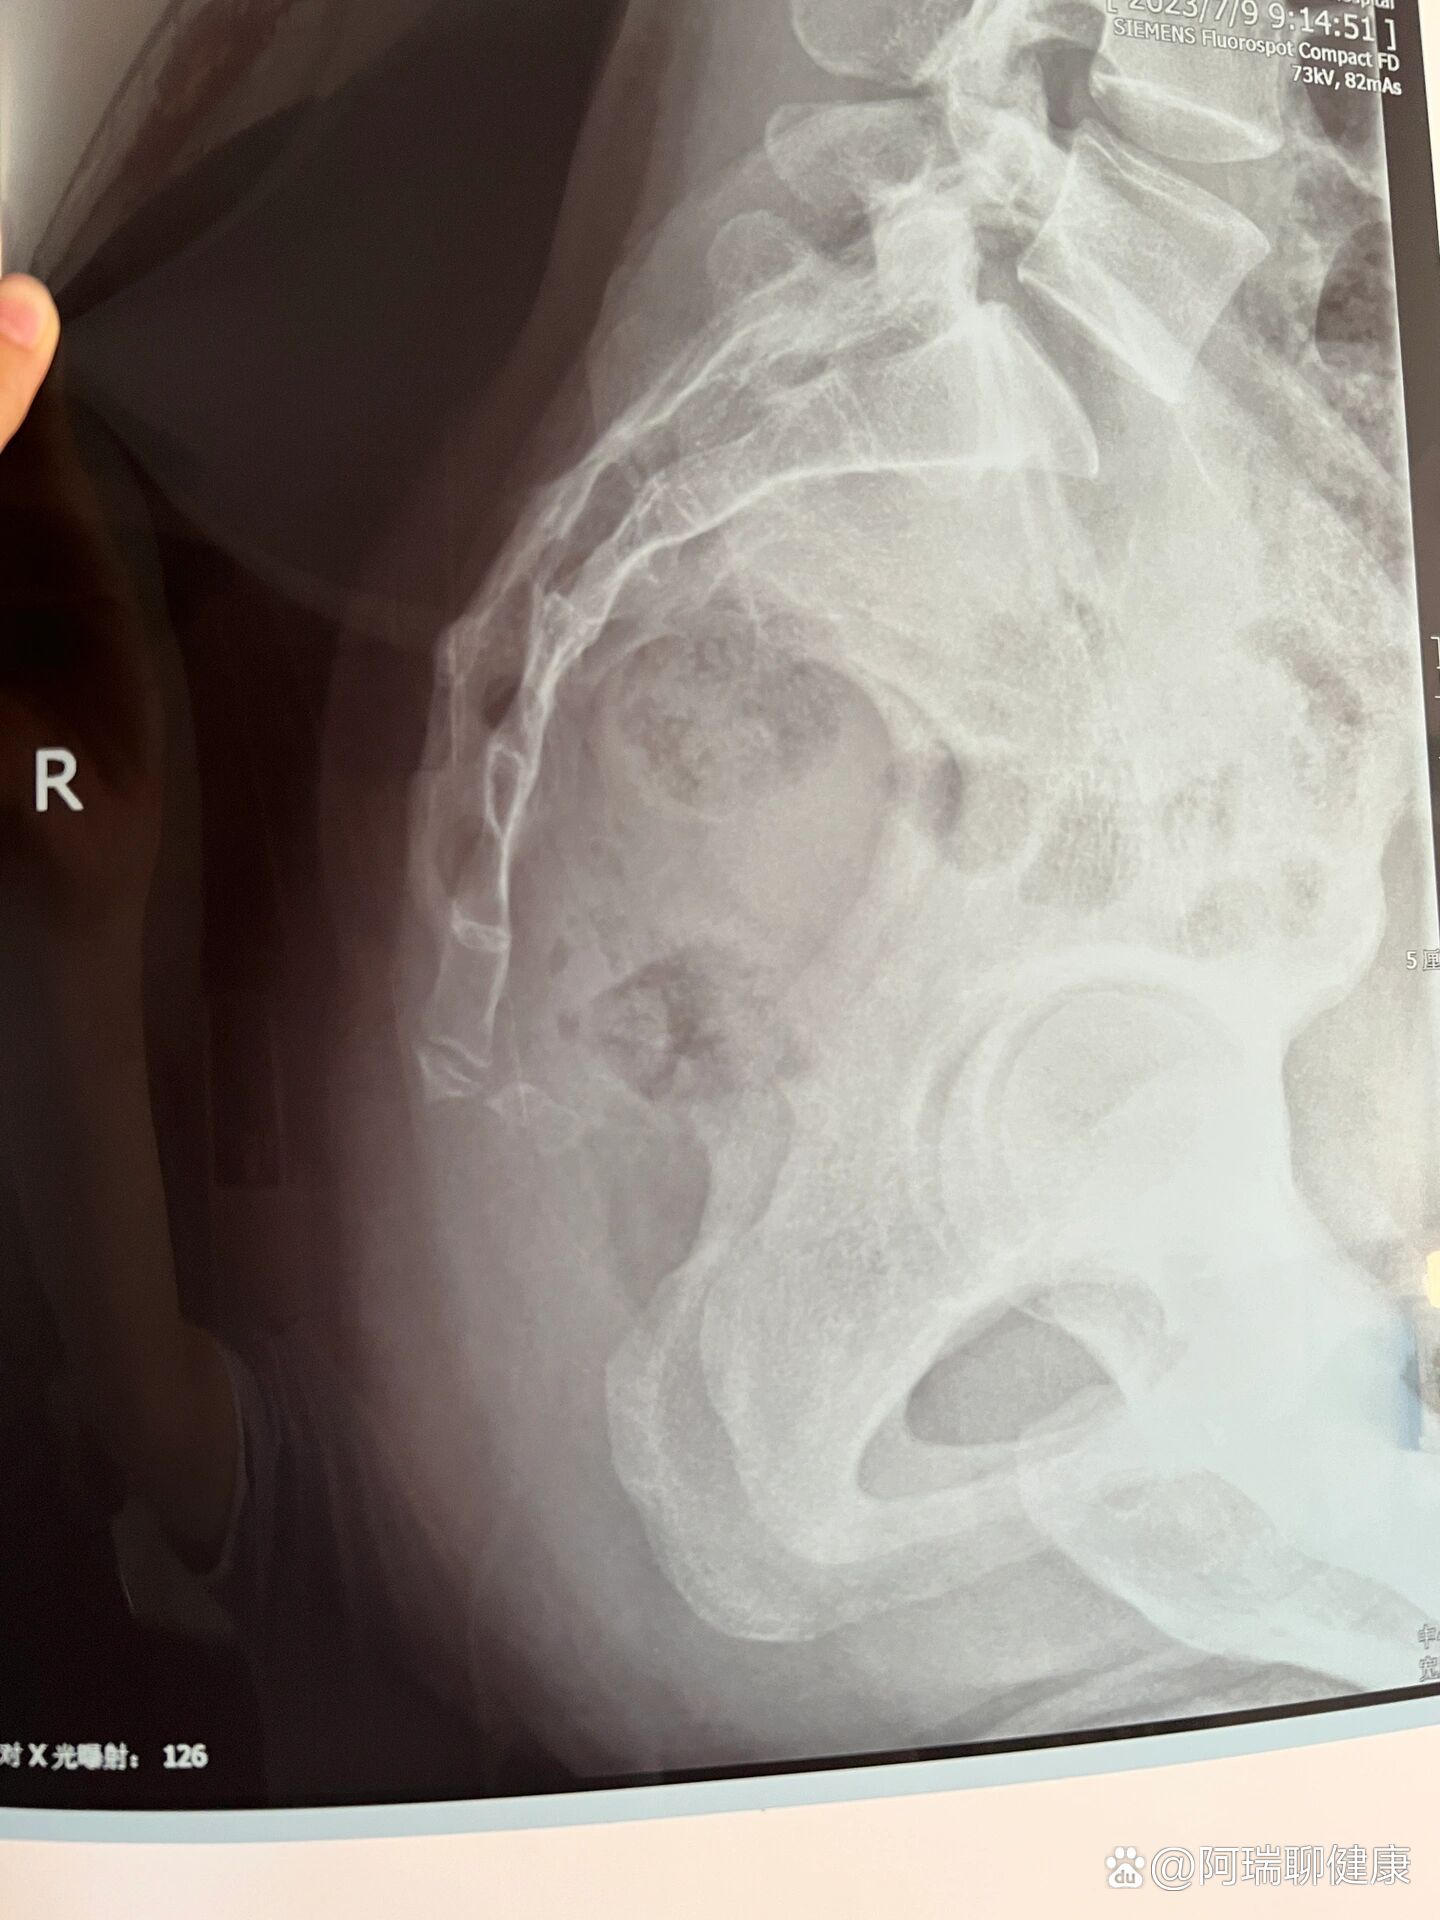

除了骶骨骨折,原来尾椎骨移位了不止一点点

骶尾骨骨折,不同尾骨形状有不一样的影响.#尾骨 #尾骨骨折 - 抖音